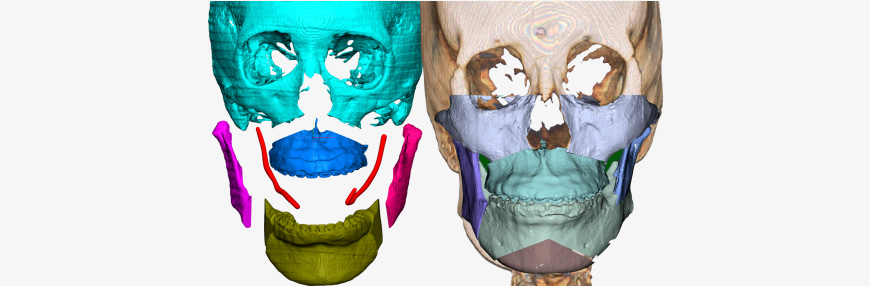

Jaw segmentation

- Skull data can be freely osteotomized according to technique preferred by oral surgeon

- Osteotomy position, range, & amount can all be adjusted depending on patient characteristics

- Combining osteotomy segments verifies anatomical changes during bone deletion & bone movement for feasible & precise surgical plan